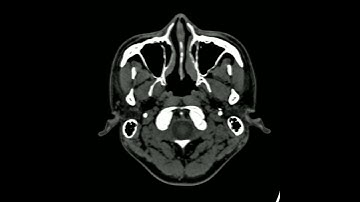

Converting DICOM to MP4 movie files: A proof of concept proposal.